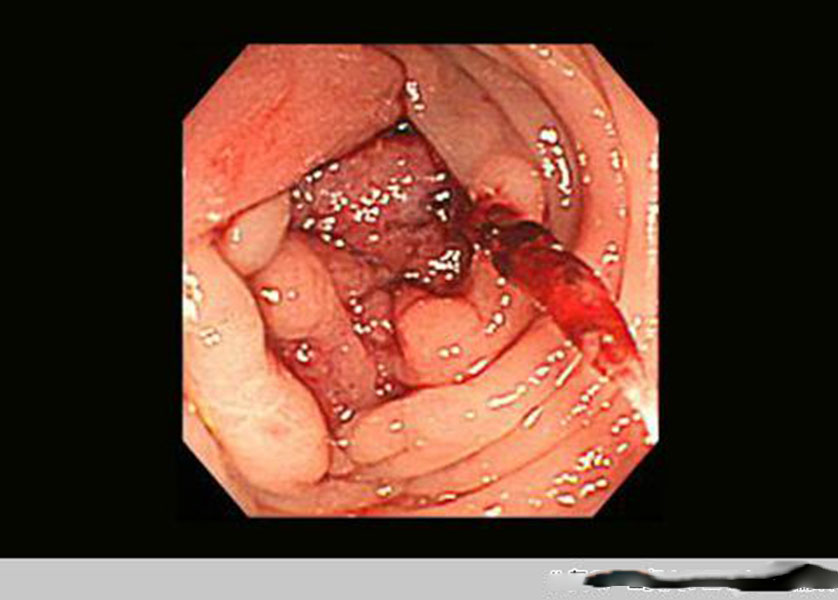

腫瘤腸腫瘤真實